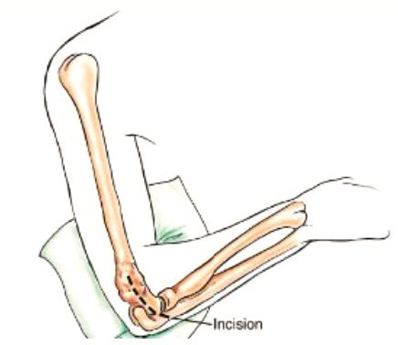

A long incision is made along the biceps muscle and the elbow joint is exposed using an s shaped incision from the long incision.

This is a picture of a patient's arm prior to surgery. The arm is marked from the shoulder to the forearm to ensure that the incision being made is long enough for the tumor to be fully removed.